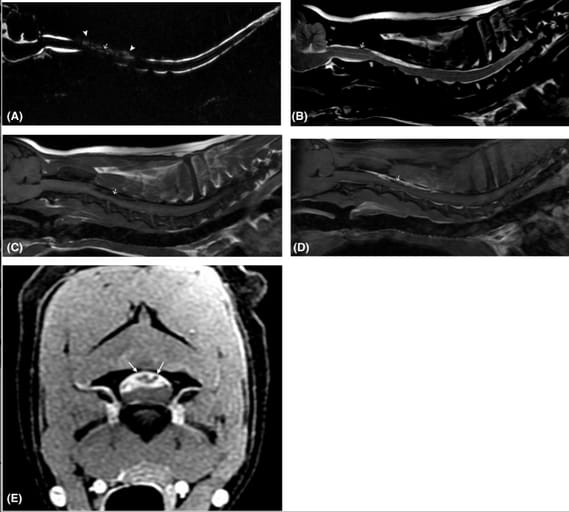

Sagittal pre- (A-C) and postcontrast (D and E) MRI of patient 2 (3T, dorsal recumbency). A, FRFSE myelogram-like sequence, 1.2 mm slice thickness The loss of normal CSF signal hyperintensity at C2-4 is due to the space occupying nature of the lesion (arrowheads). The well-delineated, linear nematode is void of signal (arrow). (B) T2-W image, 2 mm slice thickness. T2-W hyperintensity predominates due to subdural edema and inflammation surrounding the hypointense nematode (arrow). C, T1-W FLAIR image, 2 mm slice thickness. The lesion is iso- to hypointense (compared to white matter). There is no evidence of early to late subacute hemorrhage. The nematode is persistently hypointense (arrow). Fat saturated postcontrast T1-W FLAIR FS+C image (D) 2 mm slice thickness; and transverse T1-W FSPGR FS+C image (E) 2.4 mm slice thickness. Avid dural enhancement surrounds the nonenhancing nematode (arrow, D). In cross section, the coiled, non-enhancing, compressive nematode has a pinpoint intradural architecture (small arrows, E). These image features were consistently seen in all four dogs and were interpreted to be representative of the lesion